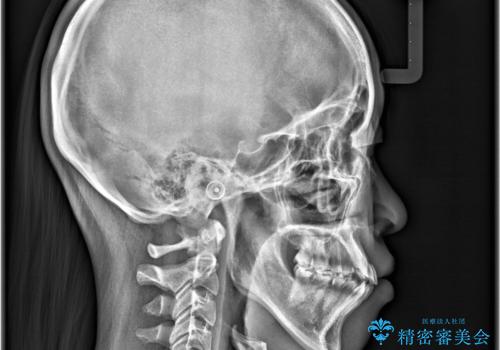

レントゲンの検査において、前歯も外側に傾いてる結果であったため、上下左右の小臼歯を抜歯して配列を行いました。